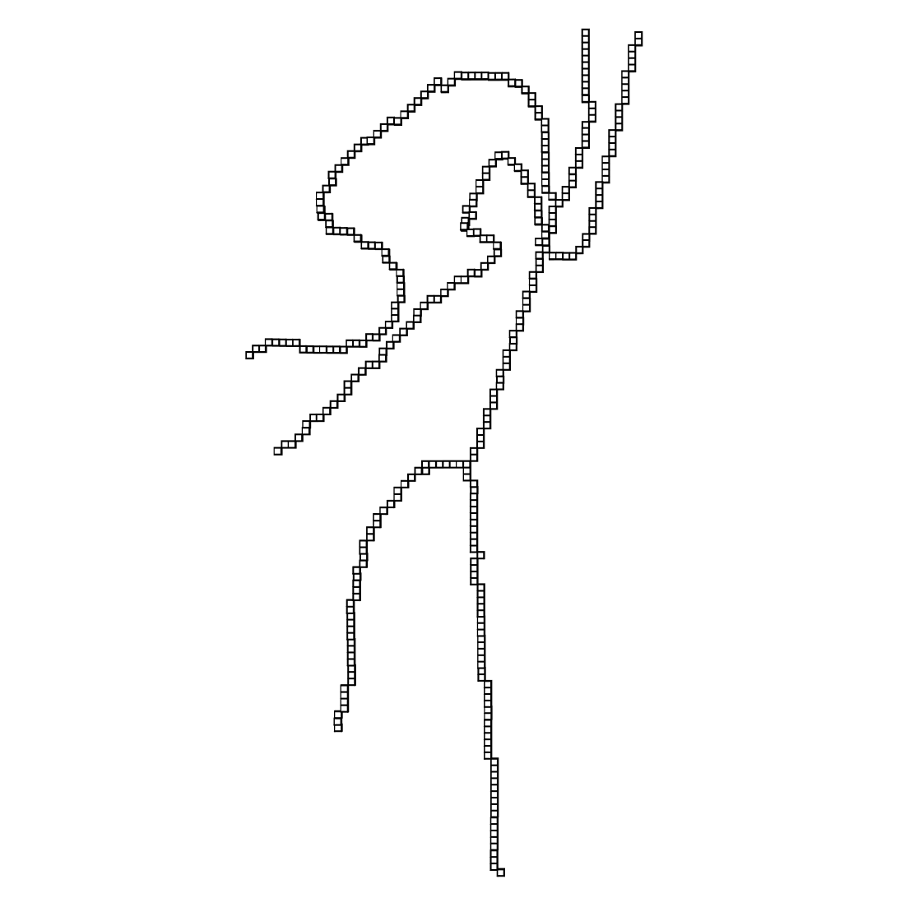

the respective semiaxes’ lengths. Conversely from , which is indeterminate, the tensor field is a symmetric positive definite (SPD) matrix for any . Here, the definition of the tensor kernel in (4) can be further reformulated exploiting the intrinsic log-concavity of . By mapping , a convex quadratic form is obtained, so that is an SPD, as the modelled tensor . In either case, the manifold of tensors can be mapped into a set of 6 independent components in the Log-Euclidean space, which greatly simplifies the computation of Riemannian metrics and statistics. We refer to [3] for a detailed methodological description. The continuous and smooth tensor field inherits the steerable property. Similarly to diffusion tensor MRI, the kernel shows a preferred diffusion direction for a given energy potential, e.g. the scalar function itself (fig. 1). This allows to define an arbitrary dictionary of filtering kernels (DFK) that embeds anisotropy and high-order directional features to scalar curvilinear templates, which enhances and locally resembles typical, smooth vessel patterns. Together with the arbitrary SLoGS DFK, we also introduce an extra pair of non-curvilinear kernels for completeness. These are the pseudo-impulsive , an isotropic derivative filter given by the Laplacian of Gaussian of , representing a Dirac delta function for . Also, the uniformly flat is another isotropic degenerate case, where the Laplacian of Gaussian derives from , which is assumed to be a uniform, constant-value kernel for . The purpose of introducing the extra kernels is to better contrast regions that most likely relate to vessel boundaries and to image background, respectively. Although and have singularities, ideally they represent isotropic degenerate kernels. Therefore we associate pure isotropic tensors for any given , so that (Identity). The respective directional kernel bases are undetermined.

Fig. 3 shows the connectedness of vessels recovered from state-of-the-art vascular enhancers and curvilinear ridge detectors FFR and OOF together with the proposed CVM for the synthetic HCP and the real PC images.

On the synthetic phantom, FFR shows a fragmented and rough vesselness response in correspondence of irregularly shaped sections of the structure. Also, the response at the bifurcation is not smoothly connected with the branches (triangular loop). Conversely, OOF recovers the phantom connectedness at the branch-point, and the vesselness response is consistent along the tortuous curvilinear section, however ghosting artifacts are observed as the shape of the phantom becomes irregular (C-like) or differs from a cylindrical tube. Also, close convoluted structures, which change scale rapidly in the HCP, produce inconsistent responses of OOF (fig. 3). CVM shows here a strongly connected vesselness response in correspondence of both regular and irregular tubular sections, with local maxima at structures’ mid-line. The connectedness of the structures is emphasized regardless the complexity of the shape, and it resolves spatially the tortuous curvilinear ‘kissing vessels’ without additional ghosting artifacts, despite the smooth profile.

Similar results are observed on the PC dataset: FFR has a poor connected response in the noisy and low-resolution image. Vessels are overall enhanced, however thin and fragmented structures remain disconnected. Overall, the vesselness response is not uniform within the noisy structures, where maximal values are often off-centred. A more consistent response is obtained from OOF, where the connectedness of vessels is improved. Maximal response is observed at the mid-line of vessels, however, noise rejection is poor. CVM strongly enhances here the vessel connectivity. The fragmented vessels of PC have a continuous and smooth response in CVM with higher values and a more defined profile. Large vessels shows solid connected regions with local maxima at mid-line as in OOF. Conversely from OOF, CVM shows improved noise rejection in the background.

The respective tensor fields (TF) synthesized on both HCP and PC show consistent features. The TF’s characteristics are in line with the connectedness of CVM: enhanced and connected vessels are associated with high anisotropy, whereas background areas show a predominant isotropic component.